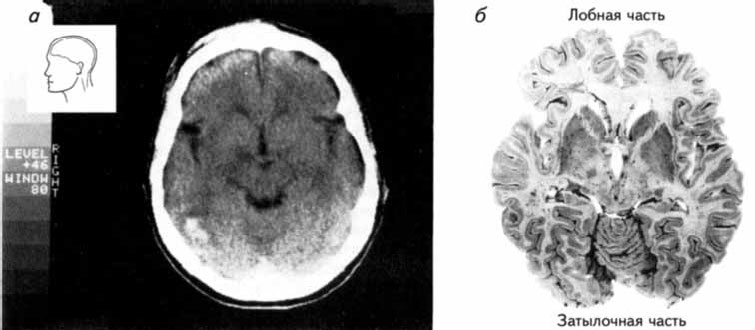

Рис. 2.13. Сканирование с помощью метода компьютерной томографии (Carlson, 1992).

В установке, предназначенной для компьютерной томографии, источник рентгеновских лучей вращается в одной плоскости вокруг головы, а рентгеновские детекторы постоянно регистрируют интенсивность проходящего сквозь голову излучения. Компьютерные программы преобразуют полученные данные в рисунки срезов мозга различной глубины (рис. 2.14). Толщина подобных срезов может не превышать 5 мм.

Рис. 2.14. Сканирование с помощью метода компьютерной томографии.

(а) Снимок, полученный на компьютерном томографе; (б) Фотография среза мозга на том же уровне, что и на снимке, приведенном на рисунке (а) (Carlson, 1992).